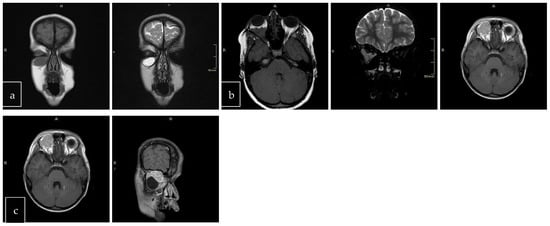

The scans at diagnosis showed masses with hypodense contrast enhancement of the tumor in all cases, with a pattern of generalized enhancement (see Figure 1). MRI at diagnosis showed low signal (isointense or hypointense) of soft tissues on T1-weighted images and high signal (hyperintense) on T2-weighted images, and gadolinium enhancement in all cases (see Figure 2). The tumor border was smooth (in 77% of cases), lobulated (10%), or mixed (13%) (see Figure 3). No association was found between tumor border type and recurrence rate or death.

Figure 2. Magnetic resonance imaging (MRI) of RMS case: T1 axial section (a), T2 (normal) axial section (b), T2 with fat saturation axial section (c), T2 fat saturation coronal section (d), and T1 post-gadolinium (e). This case represents hypothesis T1, hyperintense T2, and intense enhancement postcontrast (gadolinium).